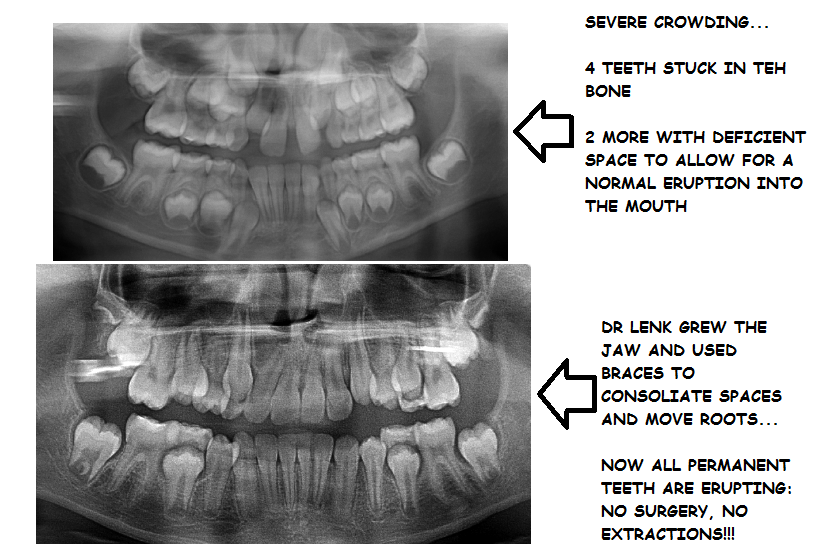

PROBLEMS CAUGHT EARLY CAN PREVENT EVEN BIGGER PROBLEMS: FUTURE SURGERY, EXTRACTIONS, AND EXPENSIVE/COMPLICATED ORTHODONTIC CARE!